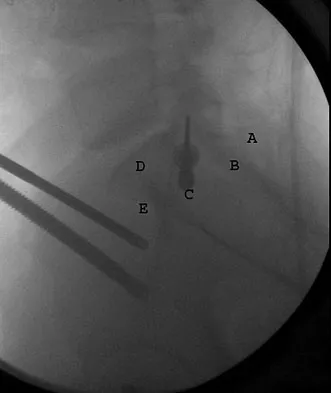

What letter in Figure 33 marks the correct starting point for a transiliac pelvic screw?